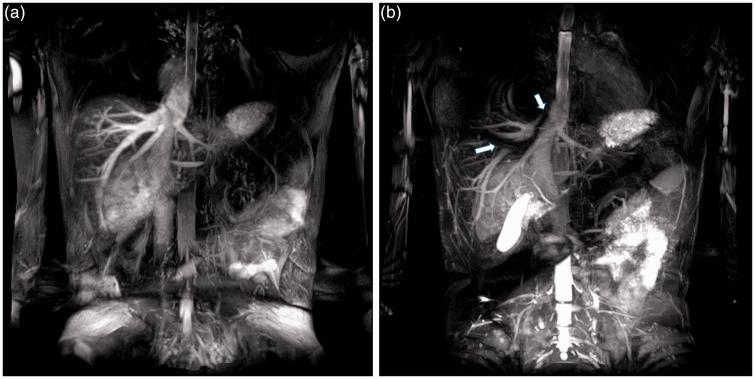

The CNRs of the main portal vein, right portal vein, and left portal vein at 3 T were better than at 1.5 T. The image quality scores for the portal branches of segment 4, 5, and 8 were significantly higher at 3 T than at 1.5 T. The CNR of the right hepatic vein (RHV) at 3 T was significantly lower than at 1.5 T. The image quality scores of RHV and the middle hepatic vein were higher at 1.5 T than at 3 T. For RHV visualization, the difference was statistically significant.

Non-contrast-enhanced MR portography with Time-SLIP at 3 T significantly improved visualization of the peripheral branch in healthy volunteers compared with1.5 T. Non-contrast-enhanced MR hepatic venography at 1.5 T was better than at 3 T.

结果

3T时门静脉主干、右门静脉和左门静脉的CNR优于1.5T。3T时第4、5和8段门静脉分支的图像质量评分显著高于1.5T。3T时右肝静脉(RHV)的CNR显著低于1.5T。1.5T时RHV和肝中静脉的图像质量评分高于3T。对于RHV可视化,差异具有统计学意义。

结论

与1.5T相比,3T下使用Time-SLIP的非增强MR门静脉造影显著改善了健康志愿者外周分支的可视化。1.5T下的非增强MR肝静脉造影优于3T。